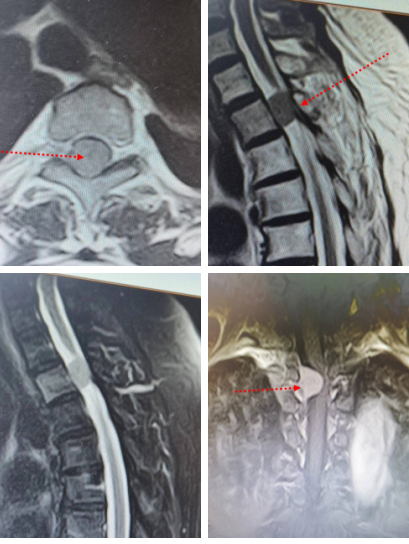

患者彭女士,自三月以来感觉自己双下肢麻木无力且运动及感觉障碍逐渐加重,脊髓核磁共振检查证实为胸2段椎管内肿瘤,遂收住入院。经MR增强扫描后发现异常信号,均匀强化明显并出现类似脑膜尾征,脊髓受挤压变薄,考虑为脊膜瘤。

术前检查